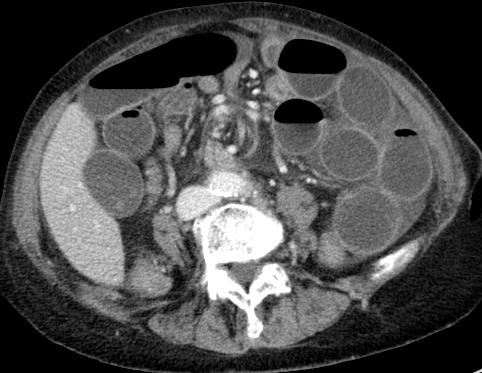

| dilated small bowels according to mesenteric swirl |

| center of the whirl is the superior mesenteric artery |